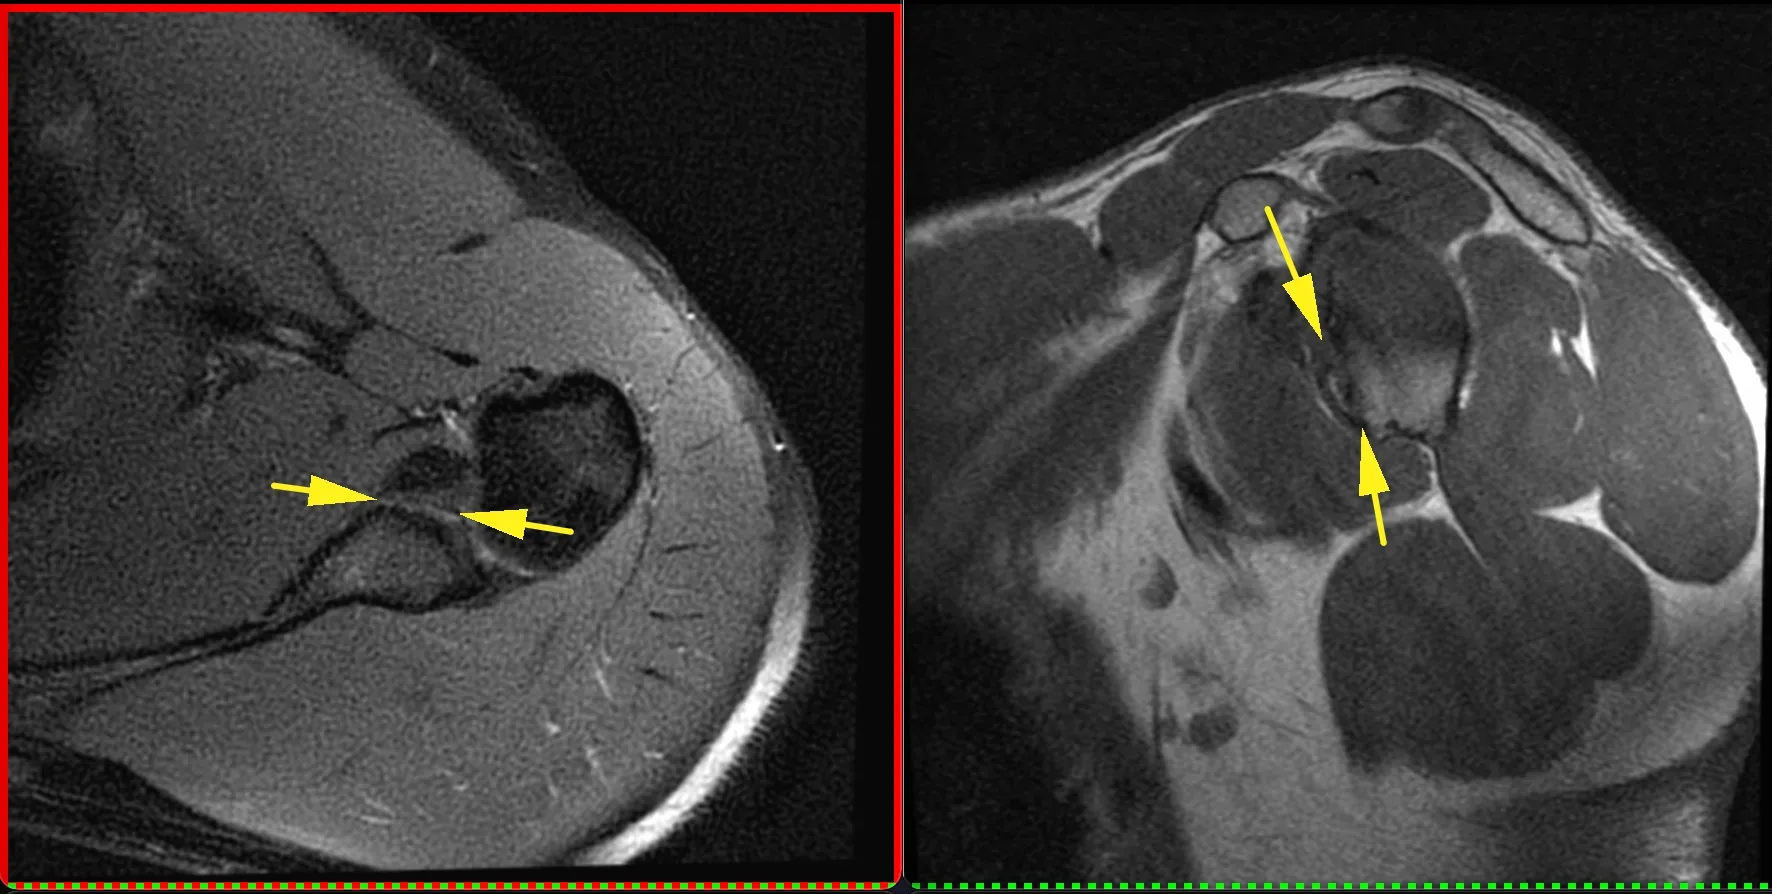

Вот такие плечики у пациента 29 лет! Во время эпидемии COVIDa-19 перенёс тяжёлую форму, лечили, в том числе, высокими дозами кортикостероидов, так что остеонекроз, который мы имеем возможность видеть в головках плечевых костей, по всей видимости, развился, как осложнение этого вида терапии. Хотя, при этой инфекции возникает ещё и гиперкоагуляция, которая и сама по себе является фактором риска развития некроза костей. В литературе такие случаи описаны и известны, есть описания развития остеонекроза даже четырёх костей одновременно (головок бедренных и плечевых костей), причём, развился он аж через полгода после окончания терапии. В нашем случае справа некроз привед к фрагментации головки плеча. Понятное дело, что функции плечевых суставов нарушены, в том числе, за счёт развития грубого вторичного артроза. Видимо, тотальная артропластика потребуется...

А вот вдогонку ещё костное повреждение Банкарта, парень 20 лет. Последствия переднего вывиха плеча.

Из-за отрыва сухожилия подлопаточной мышцы вывихнулось медиально сухожилие длинной головки бицепса. Сухожилие подлопаточной мышцы является одновременно удерживателем длинной головки бицепса в межбугорковой борозде, вплетаясь в малый бугорок плеча и как бы продолжаясь в поперечную связку (связку Броди), которую некоторые считают не истинной связкой, а частью сухожилия надостной мышцы.